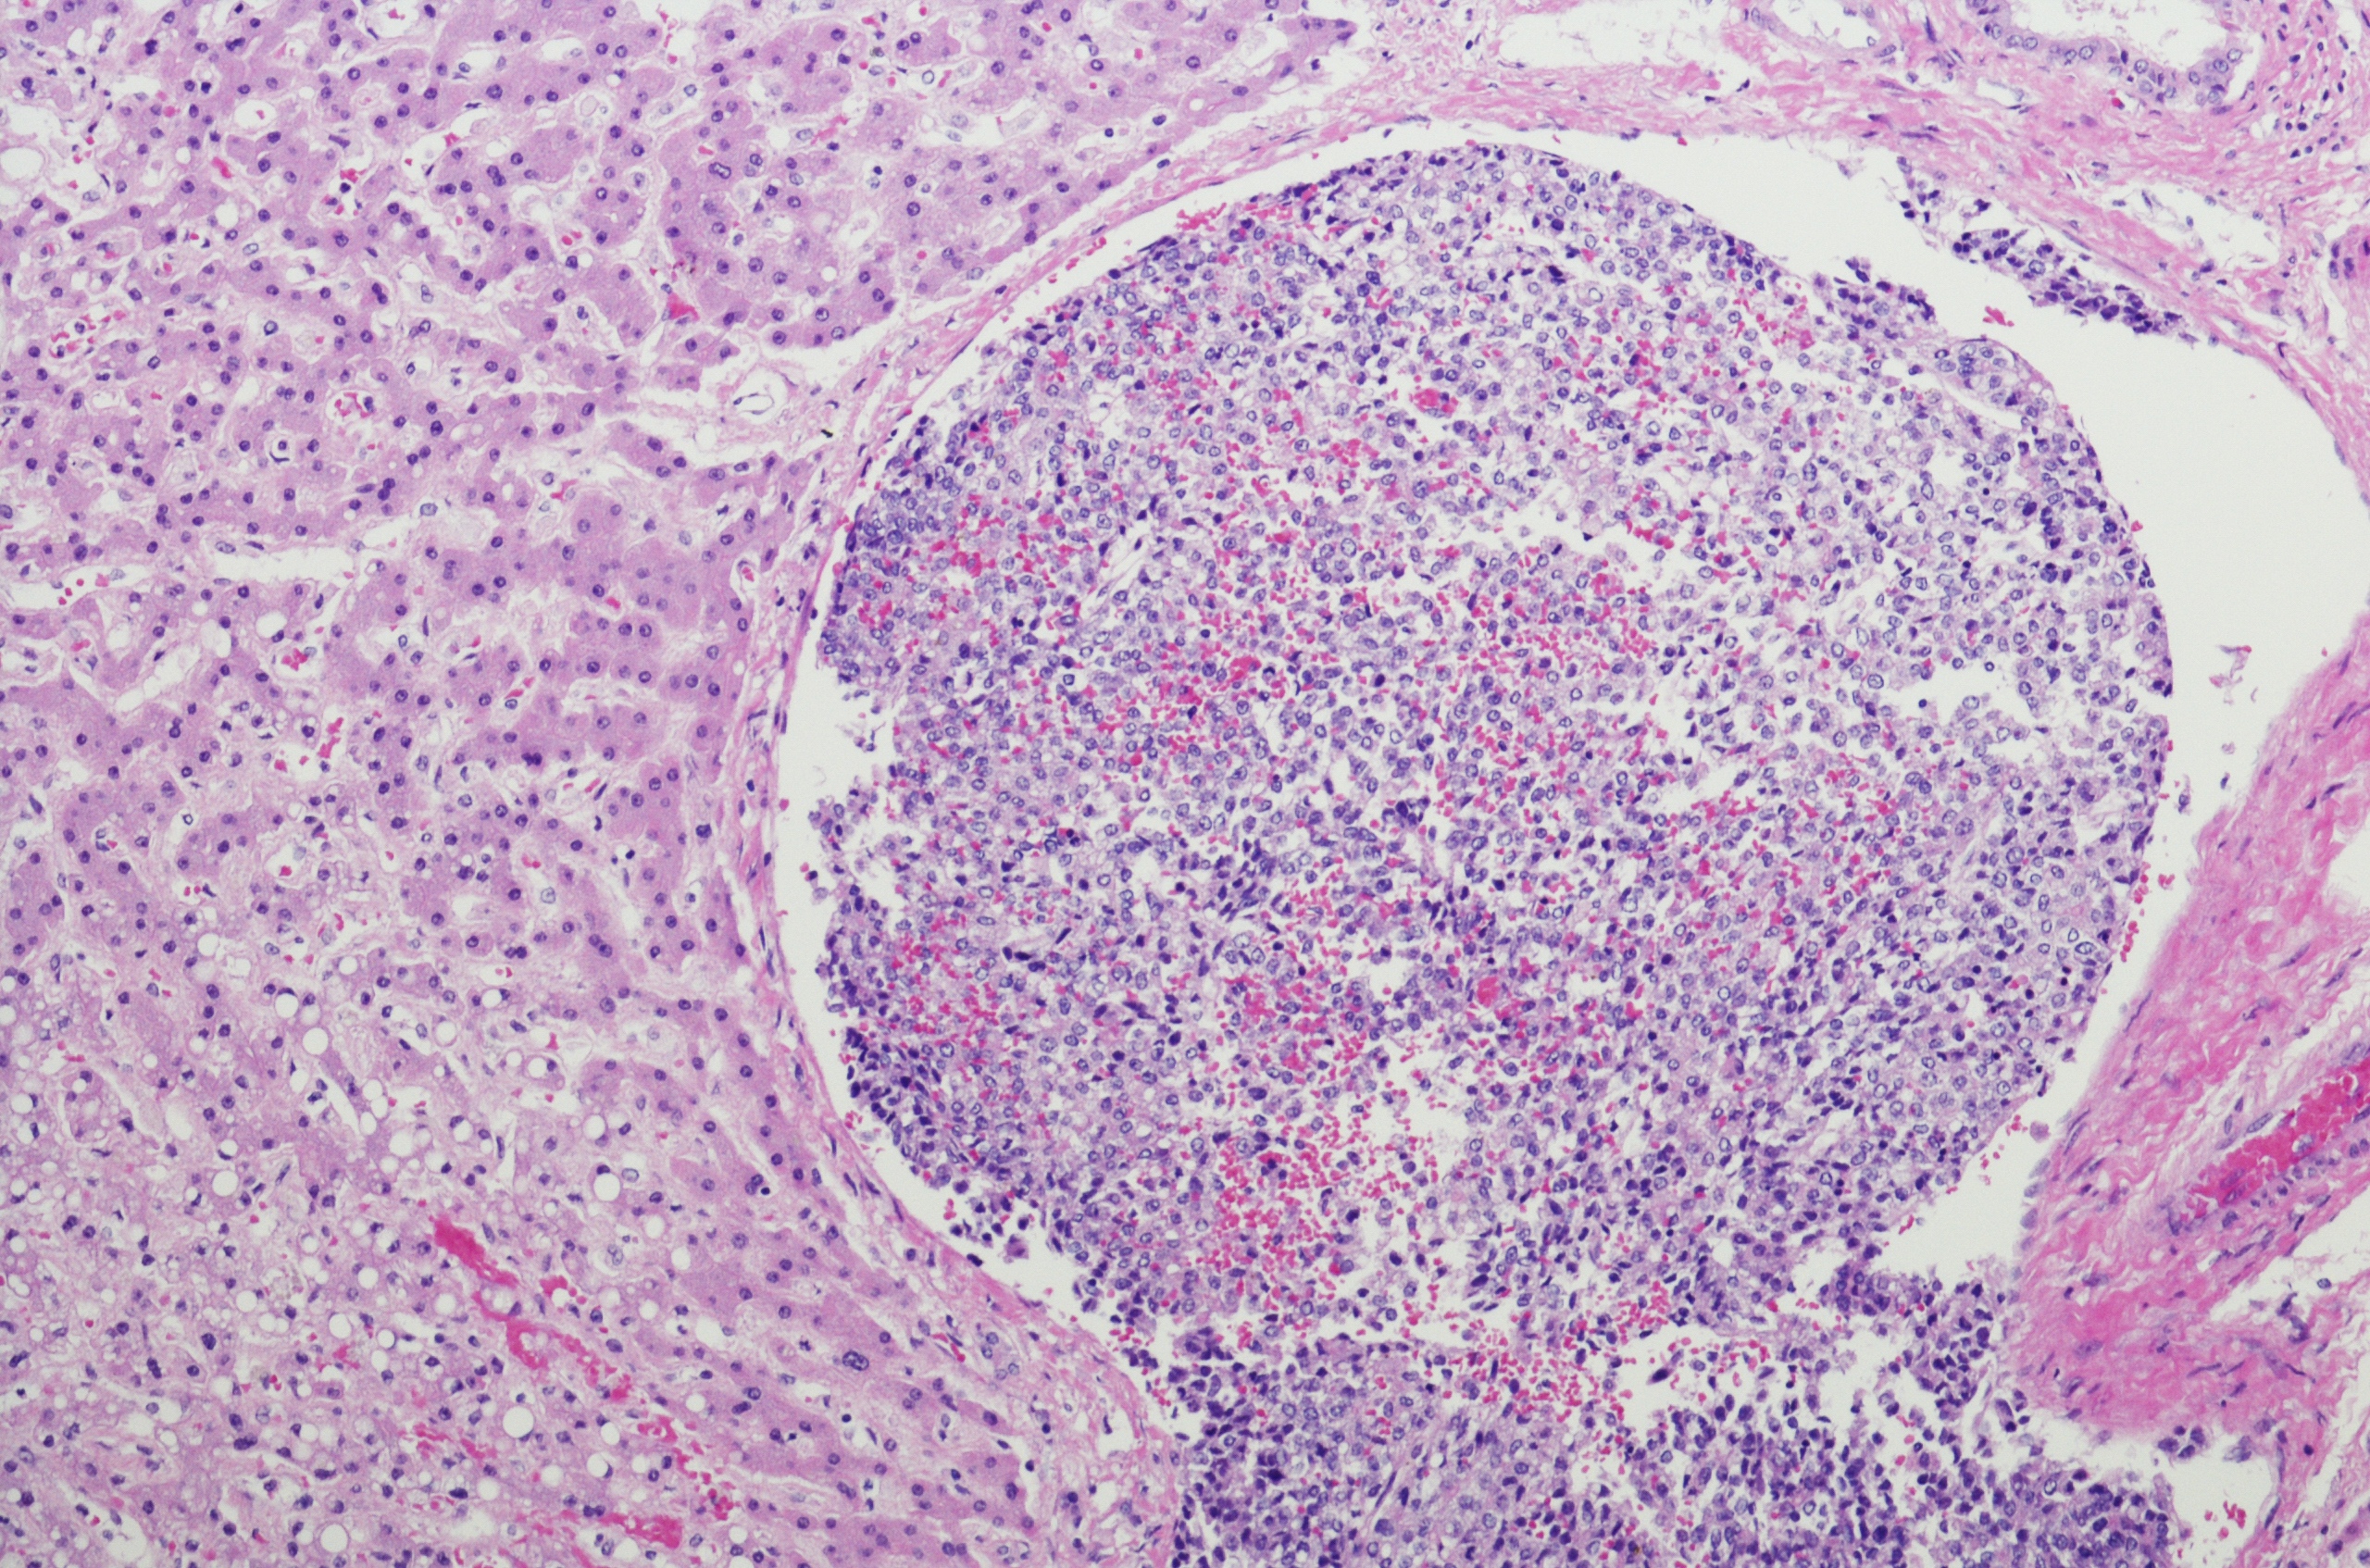

Compared with adult cancers, childhood cancers are rare and there are a number of very rare types which account for around 20-25% of all childhood cancers. Most behave like other children’s cancers, growing and spreading to other parts of the body.

Rare Children’s Cancers are broadly categorised as follows:

Rare tumours which only occur in children include: